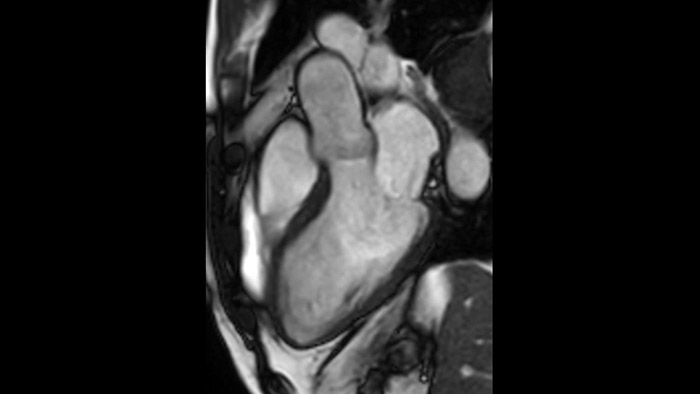

L'utilità diagnostica e prognostica della RM cardiaca è in continua crescita. È possibile valutare l'anatomia e la funzionalità cardiache utilizzando acquisizioni cine, ottenere informazioni sulla perfusione e vitalità del tessuto cardiaco, visualizzare potenziali edema con la sequenza Black Blood, accedere e persino quantificare la caratterizzazione dei tessuti con CardiacQuant.